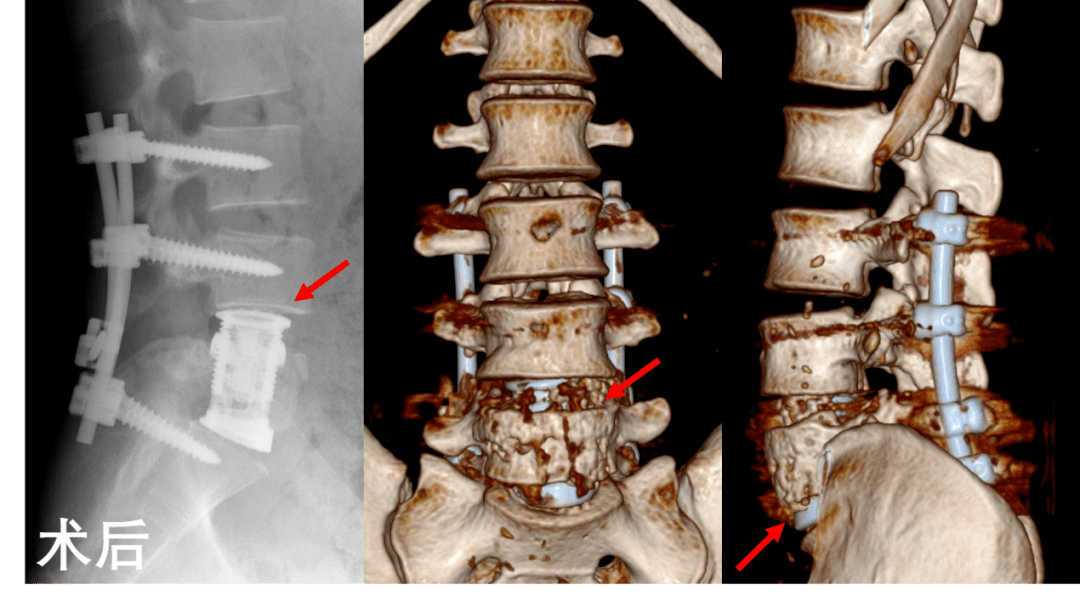

郎中日记椎体压缩高度丢失如何复位

新闻嘉一首例后路一期椎体切除减压人工椎体植入术重建青年的人生脊梁